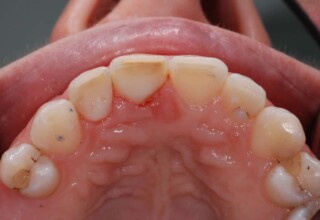

Αποκατάσταση Οπίσθιου Απονευρωμένου Δοντιού με Ανασύσταση Σύνθετης Ρητίνης

Η συνήθης αποκατάσταση ενός απονευρωμένου οπισθίου δοντιού είναι με μια στεφάνη. Ο κύριος λόγος είναι η προληπτική προστασία από κάταγμα και την επακόλουθη εξαγωγή. Σε πολύ συγκεκριμένες περιπτώσεις όπου εξειδικευμένα κριτήρια (κυρίως η ποσότητα της εναπομείνουσας οδοντικής ουσίας) ικανοποιούνται ή όταν η οικονομική δυνατότητα του ασθενή το επιβάλει, μια εκτεταμένη ανασύσταση συνθέτης ρητίνης μπορεί ν’αποκαταστήσει την αισθητική και λειτουργικότητα του δοντιού.